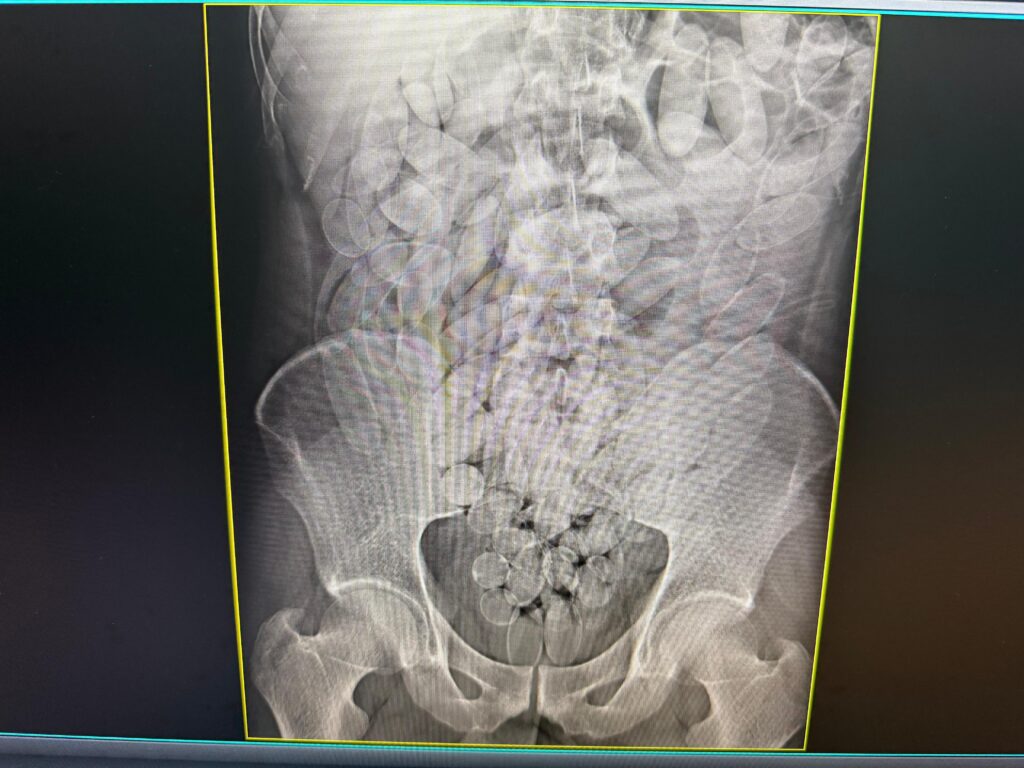

Os raios X confirmaram que o grupo havia ingerido cápsulas contendo pasta base de cocaína. Ao todo, 645 cápsulas foram retiradas por meio de procedimento médico. Após o atendimento, os envolvidos foram encaminhados à Polícia Federal, que conduz a investigação.